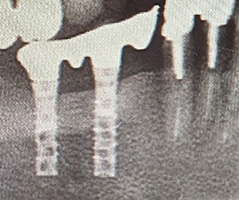

第1号インプラント(1993年7月8日手術)

それから32年、現在も1mmの骨吸収もなく、何の問題もなく安定して今日まで機能し続けており当院にとって歴史的な症例となりました。チタンインプラントの信頼性が証明されました。

32年経過症例 / 91歳(2025年現在)・女性

1993年 下顎インプラント埋入時(59歳)